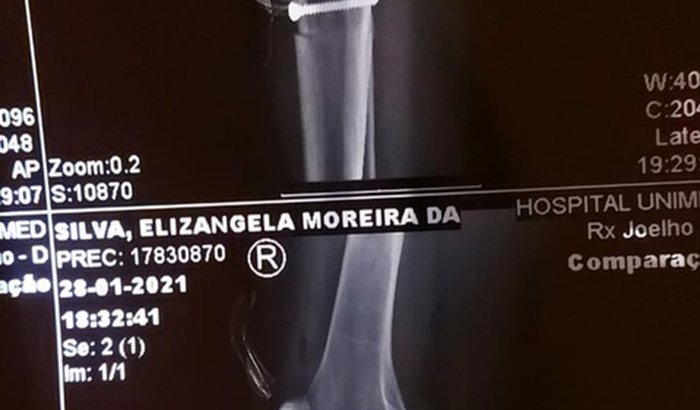

Tenho fotos da cirurgia, raio X aonde mostra que foi colocado uma placa com 2 parafusos para realinhar a patela. E o laudo dos procedimentos que foram feitos. Para quem caso não saiba o que é uma mosaicoplastia; é implante de cartilagem. Foram feitos esses procedimentos no meu joelho direito. Implante de cartilagem, enxerto atrás da patela, realinhamento patelar, aonde foi preciso por a placa e os parafusos para sustentação da mesma. Agradeço quem puder me ajudar nesse momento difícil que estou passando. Fiz a cirurgia dia 28/01/2021. Sou sozinha, tenho um irmão que está me ajudando como pode. Pago aluguel e realmente não tenho condições financeiras para deslocamento até a clinica. Agradeço de coração a todos que podem me ajudar e que Deus multiplique 100x mais na vida de vocês.....